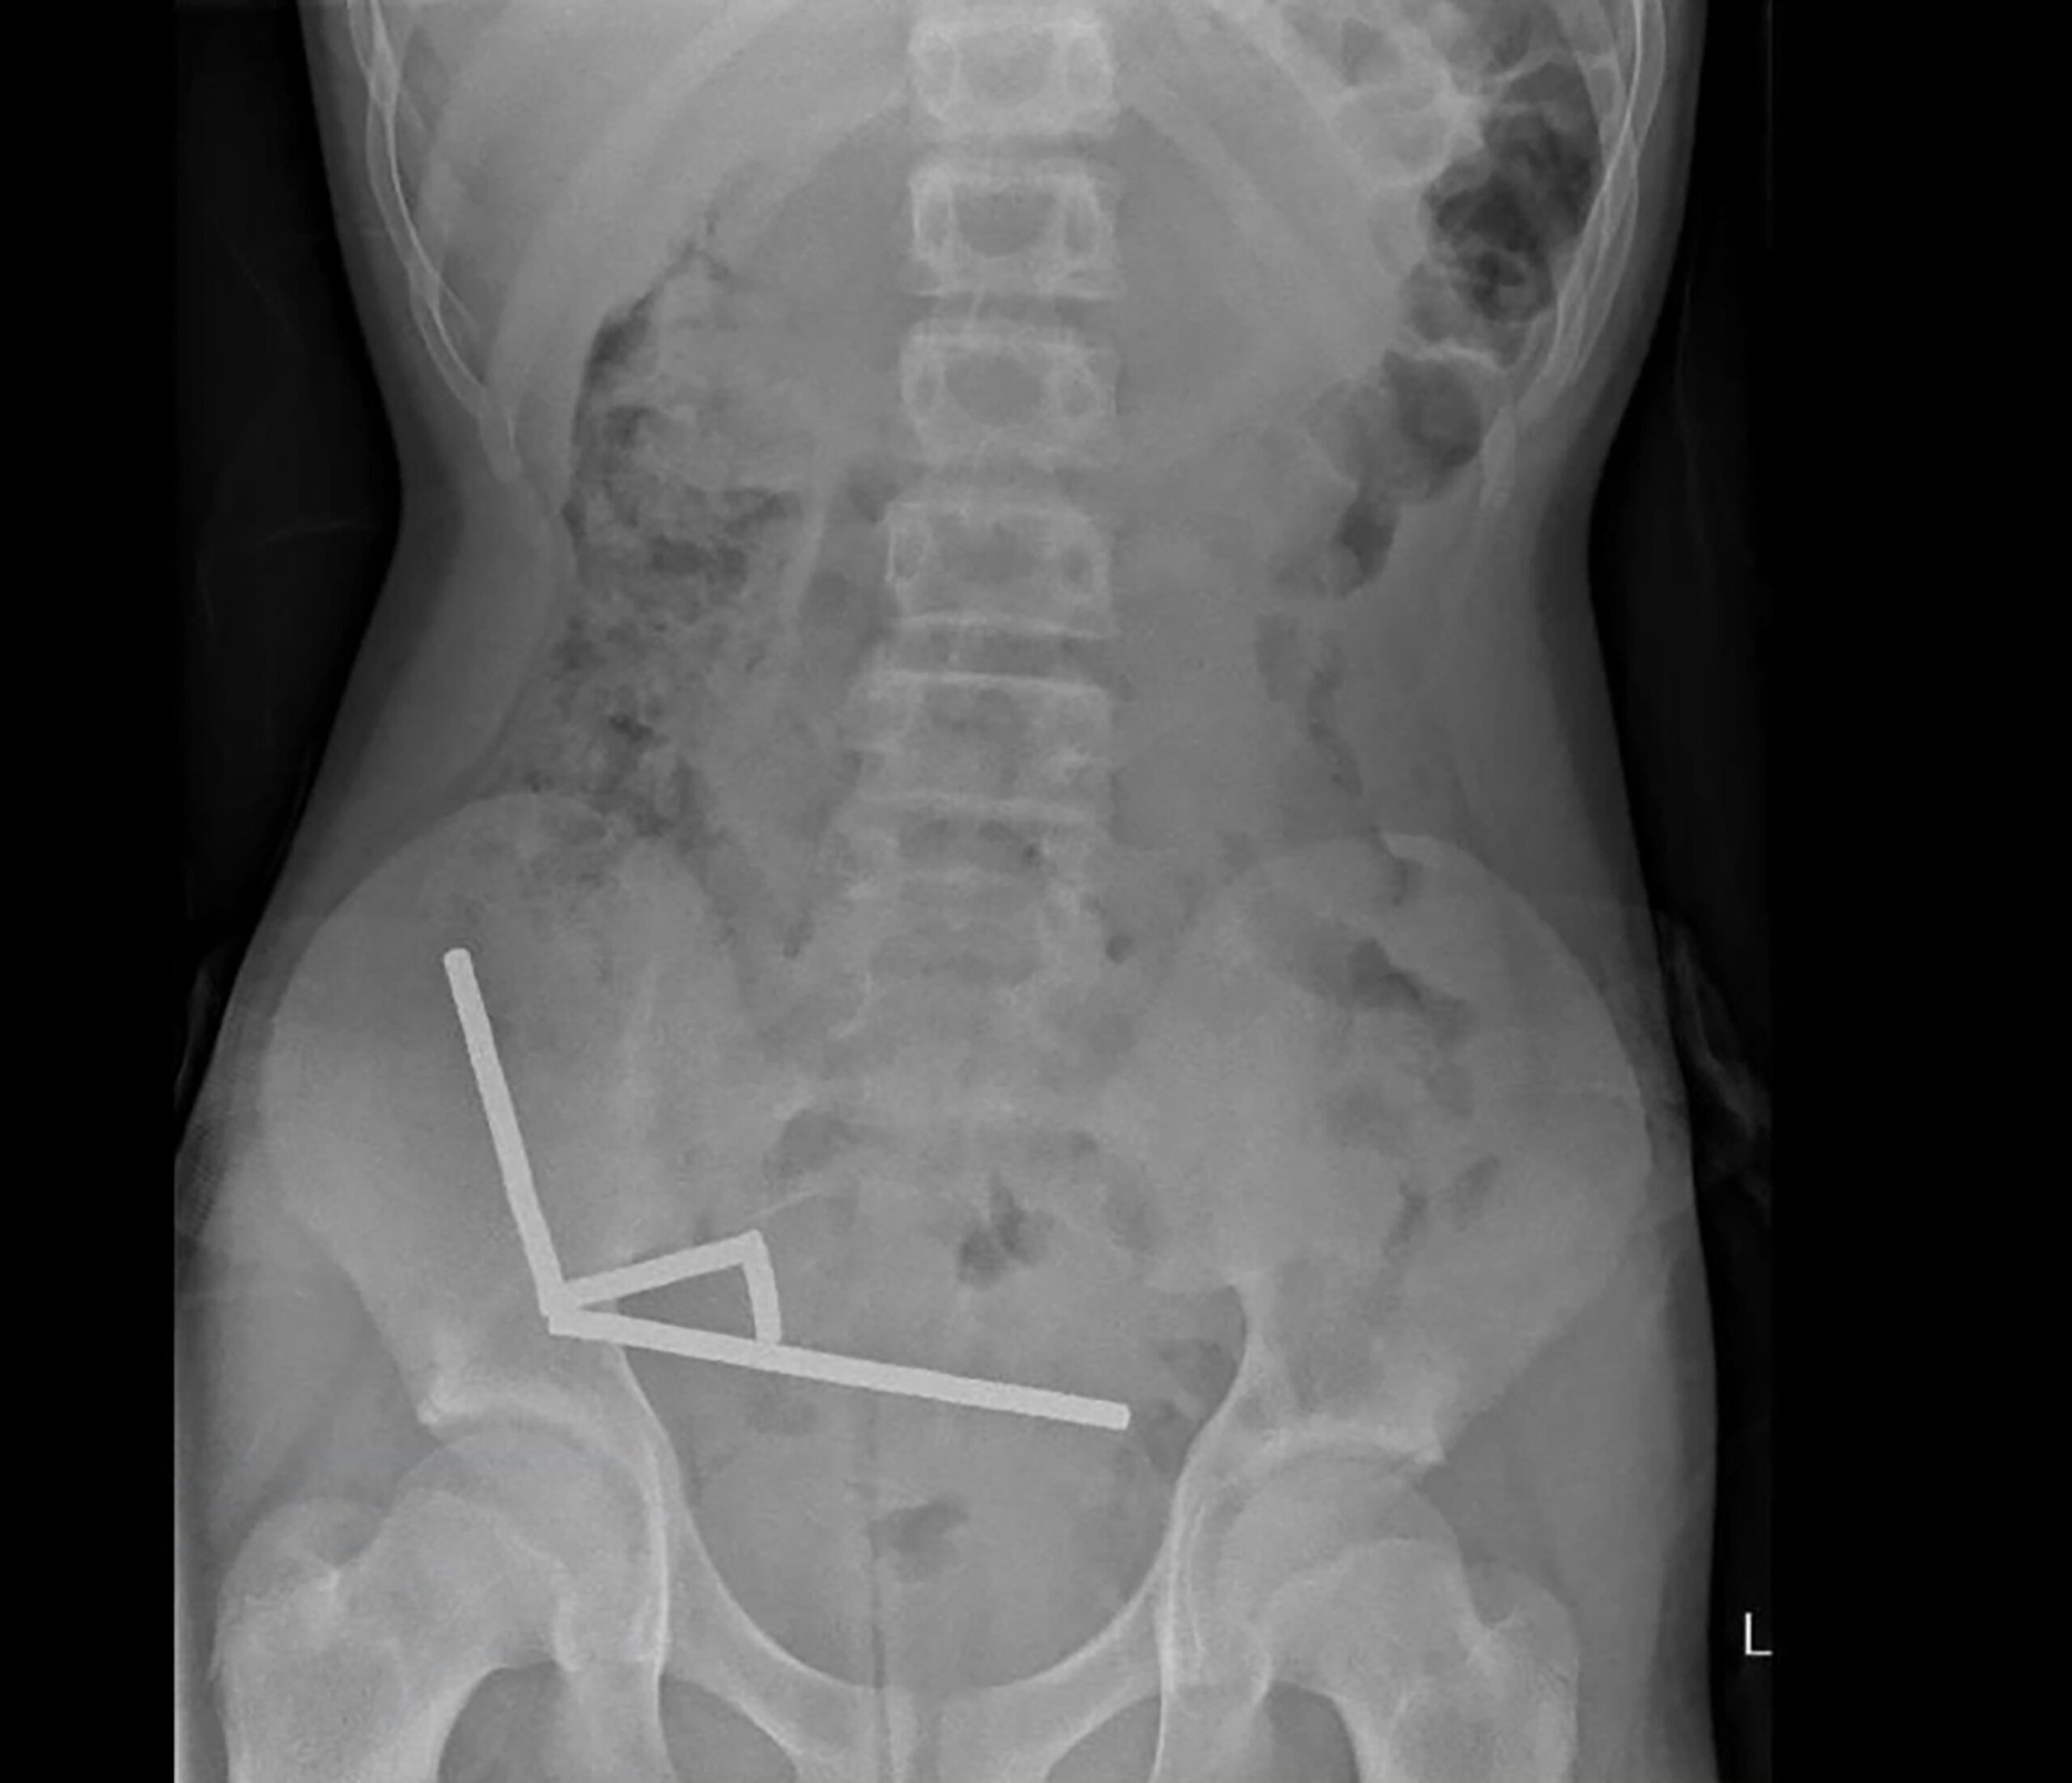

Hasil imbasan menunjukkan magnet-magnet itu bergumpal membentuk empat rantai di bahagian bawah kanan abdomen, menarik bahagian-bahagian usus antara satu sama lain dengan daya magnetnya.

Sebahagian imej imbasan juga terganggu akibat kehadiran magnet, kata laporan itu.

Doktor mendapati rantaian magnet itu menyebabkan kematian tisu pada empat bahagian usus kecil dan besar.